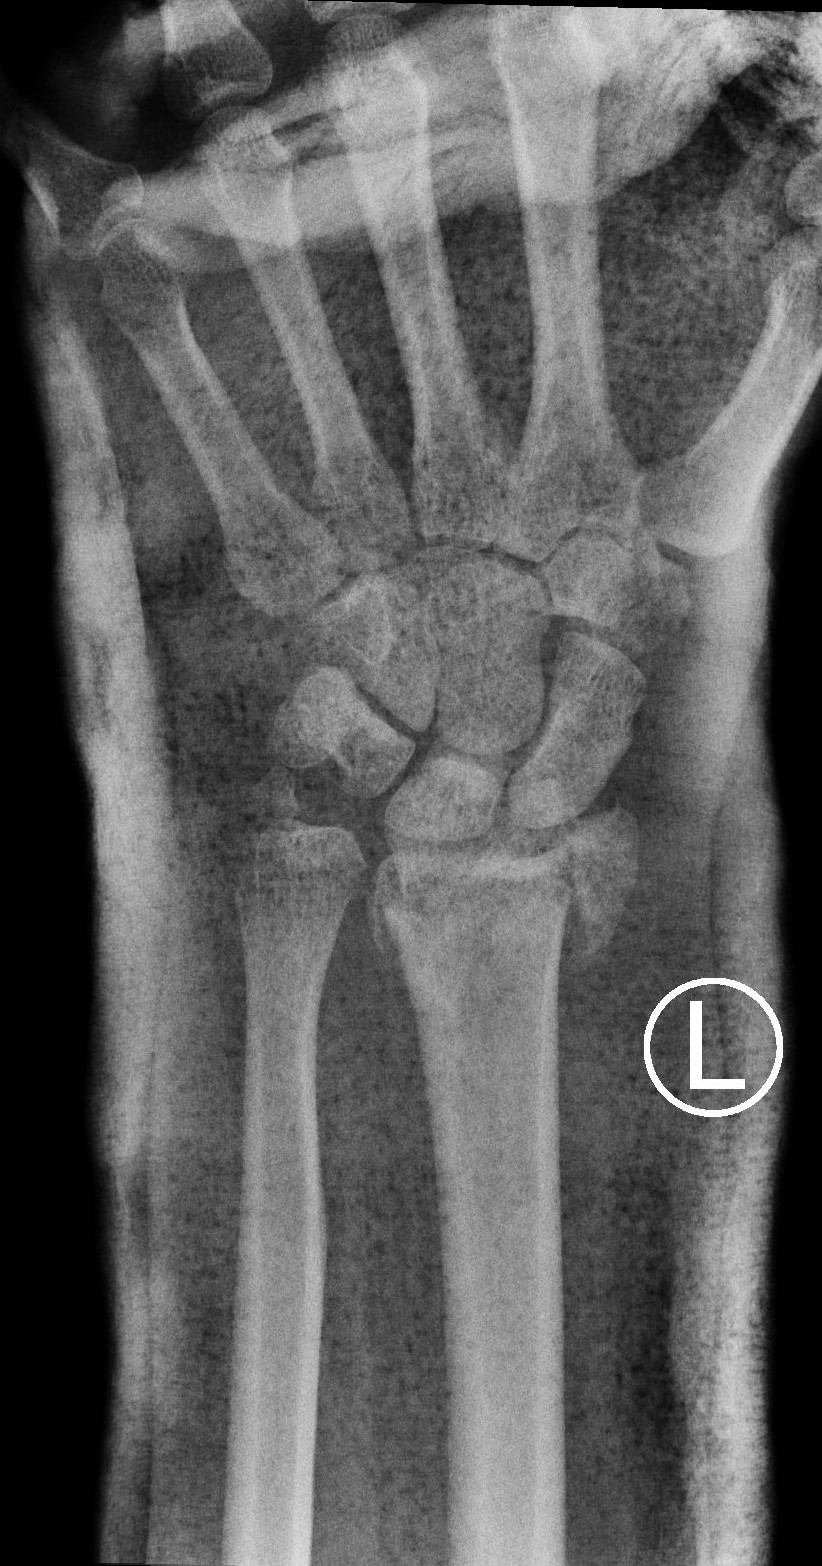

Successful surgery to reduce and fixate with the plate of neglected, displaced fracture of the distal radius

Treatment of neglected, displaced or united distal radial fractures (DRFs) is difficult, because it requires either wedging the almost consolidated fracture and reduction to the correct position, or cutting the united bone and putting it in the correct position (corrective osteotomy). Both treatments are associated with the risk of failure and complications. The paper presents a case of almost fully united DRF in a man, in whom 5 weeks after the injury, and after unsuccessful primary fixation with K-wires, the bone fragments were surgically wedged, aligned and fixed with a palmar plate. The result of treatment after 2 months was satisfactory. Early surgery allowed for a significant shortening of the recovery period and allowed the patient to return to work.